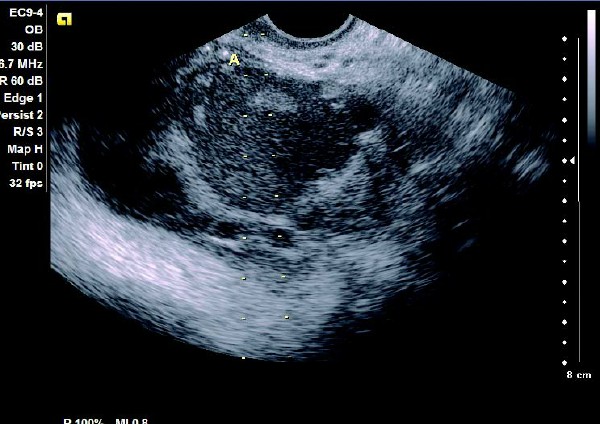

卵巢巧克力囊肿彩超描述,卵巢巧克力囊肿的超声诊断要点 2.多囊型:呈现多个圆形或不规则无回声区,无回声区中有散在细小光点,其内有单个或多个光带回声,囊壁增厚,内壁欠光滑。CDFI 检测:囊壁和分隔可见条状血流信号。

患者,女,35岁。每次月经量少,痛经,近来行经期延长、疼痛加重来院诊治。超声报告显示子宫前倾位,子宫体大小为:5.9cm×5.1cm×4.8cm,形态规则,边界清晰,宫避回声匀称,宫腔线居中,内膜厚度0.6cm,宫内未见异常回声。右侧卵巢内可见大小约5.2 cm×4.9cm的无回声区暗区,壁厚,内壁欠光滑,内见密集细光点,边界清晰。CDFI探测囊壁及囊腔内无血流信号。

超声提示:右侧卵巢巧克力囊肿